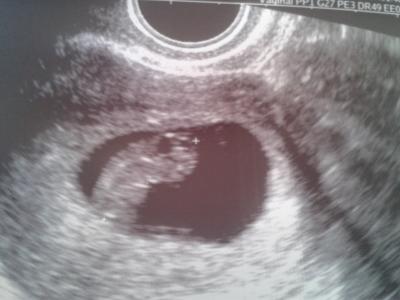

Würmchen wächst und gedeiht :-) hat jetzt 2,2cm und hat einen Kopfstand gemacht. Das Herzchen wummert ansonsten war das Kleine eher träge ;-) Das Ultraschall Gerät hat 8+5 angezeigt. Er meinte aber dass bei nur drei Tagen Unterschied zum errechneten ET keine Korrektur von ihm erfolgt. Ich soll weiter von 9+1 ausgehen. Auch gut :-)

Bild zu Zurück vom FA - Forum für März - Mamis